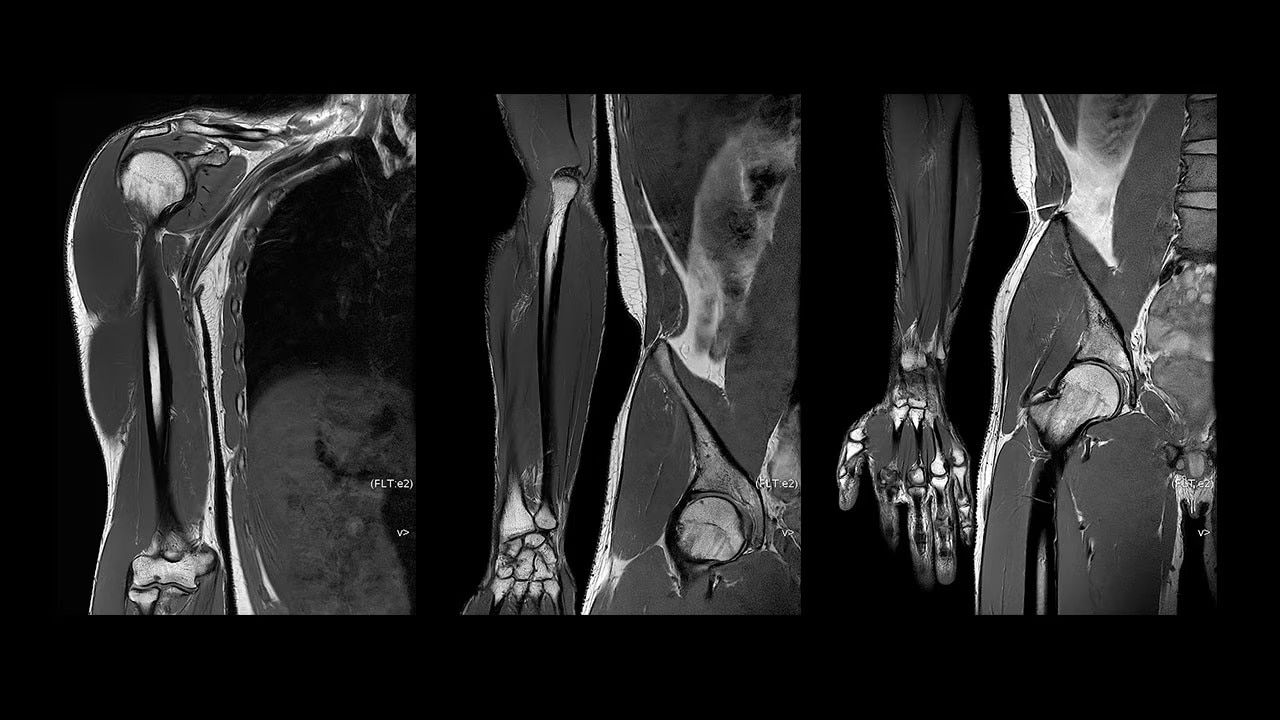

With access to the latest advanced AI technology, you can scan all anatomies and achieve pin-sharp images. Our pioneering deep learning-based reconstruction algorithm AIR Recon DL accelerates scan time and puts patients at ease.

The improved gradient of up to 80 mT/m, 200 T/m/s provides exceptional results faster and with 146 RF channels, you can ensure uniformity for every result.